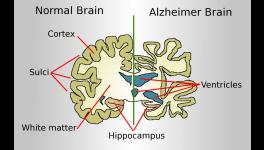

The data for the analyses were taken from clinical as well as autopsy reports on patients who succumbed to Alzheimer’s between 2005 and 2015. The confirmation of Alzheimer’s in the considered dataset was done on the basis of traditional abnormalities observed in brain autopsy (Autopsy is a detailed dissection of an organ of a deceased person and is done for determining the exact cause of the death) specimens.

These also included the presence of abnormal aggregation of proteins. It is well known that dementia patients, especially in Alzheimer’s disease, have an abnormal aggregation of a particular protein named beta amyloid, which has not been fully understood yet despite extensive research. In the study group, life expectancy ranged from one month to 130 months after the diagnosis of Alzheimer’s—most of the individuals in the study group were diagnosed on their first visit.